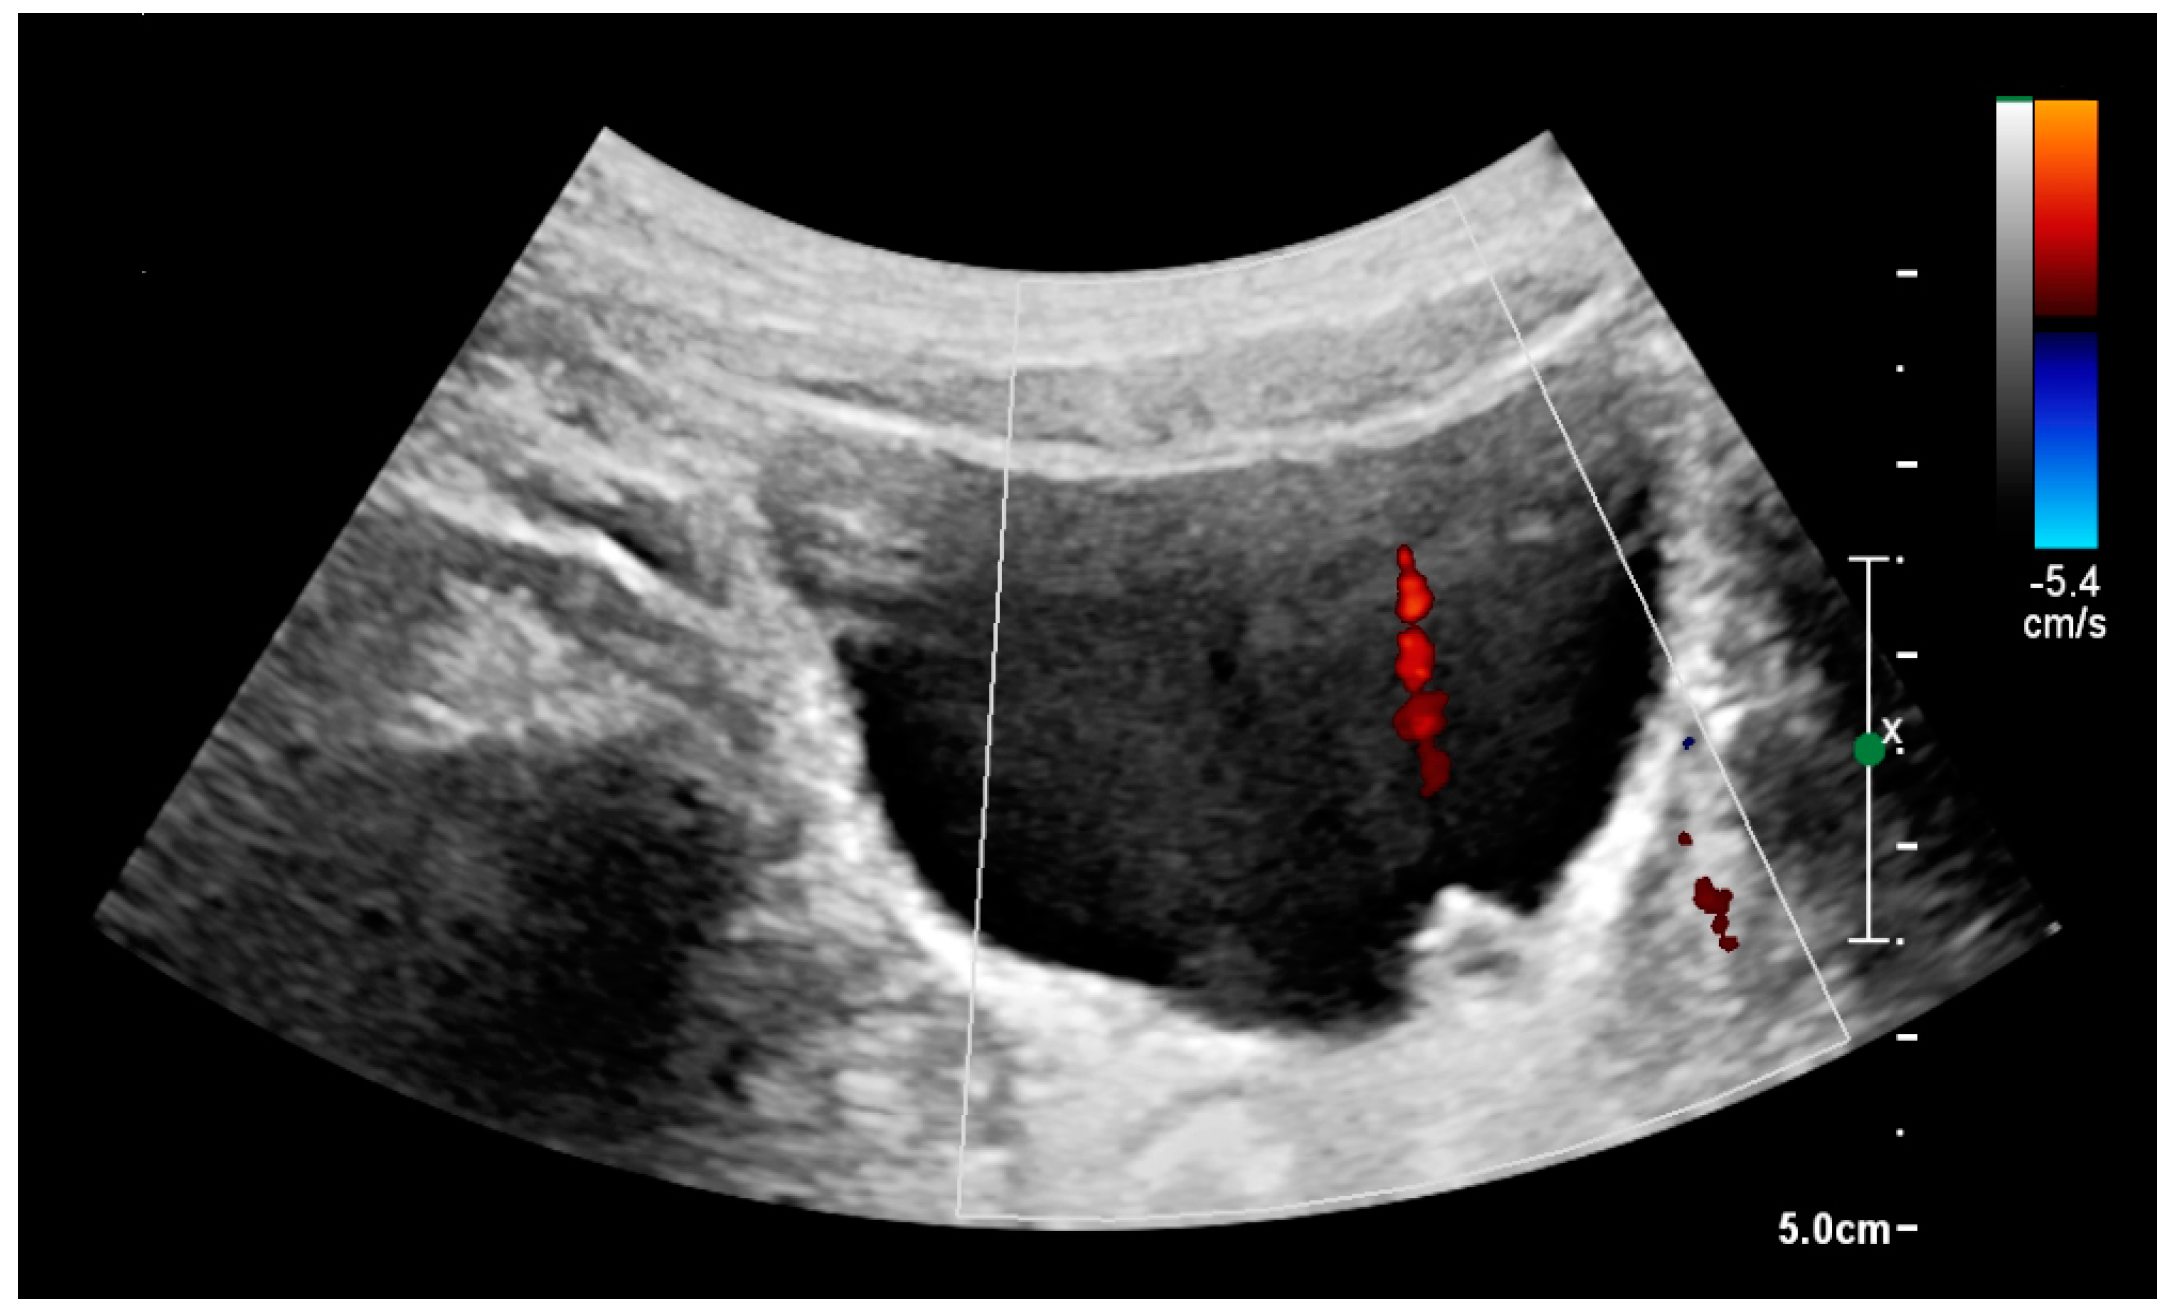

With US, larger stones (>5–7 mm) within the kidney, i.e., in the calyces, the pelvis and the pyeloureteric junction, can be differentiated, especially in the cases with accompanying hydronephrosis (Figure 18 and Figure 19) [26,29]. Hyperechoic stones are seen with accompanying posterior shadowing. Additional twinkling artifacts below the stone can often be seen using Doppler US [30]. Large stones filling the entire collecting system are called coral stones or staghorn calculi and are easily visualized with US (Figure 20). Stones in the ureters are usually not visualized with US due to the air-filled intestines obscuring the insonation window. However, ureteral stones near the ostium can be visualized with a scan position over the bladder. An exam of the ureteric orifices and the excretion of urine to the bladder can be performed by inspecting the ureteric jets in the bladder with color Doppler US (Figure 21) [4,24].

Figure 21. Left hydroureter with ureteric jet. No stone is visible. The red color in the color box represents motion towards the transducer as defined by the color bar.